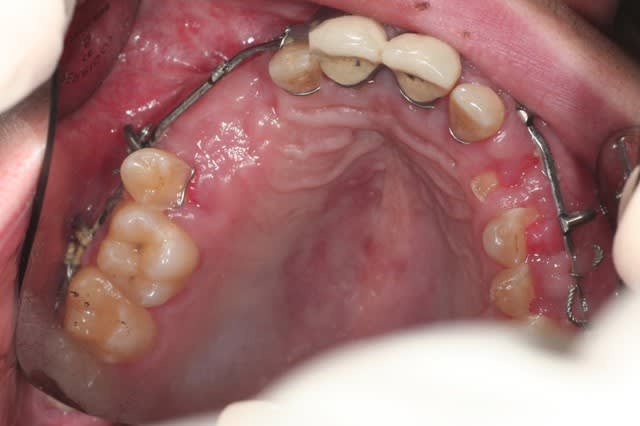

pas le temps de faire des commentaires ce matin, je balance le cas, et lâchez vous

donc, effectivement, un gros choc avec fractures multiples. effectivement marco, c'est un cas long mais qui n'a rien de sorcier en soi, je l'ai posté parce qu'il étendu et impressionnant.

ce cas n'est pas encore réalisé, je vous le livre brut de décoffrage, et j'espère le mener à bout et partager les différentes étapes sur le site.

je n'ai rien entrepris pour l'instant parce que l'ouverture buccale est très limitée, et je voudrais que le maxillo débarrasse le patient de toute la ferraille avant de commencer.

pour l'instant j'en suis à concevoir une approche, et je bute sur 36 et 37: endo + élongation + ccm, ou alors extraction? je crois que la 36 va sauter, mais 37 m'embête.

autre chose qui m'embête, c'est d'être obligé d'attendre la dépose des mini-plaques avant de pouvoir implanter 23 , 24 et 13.